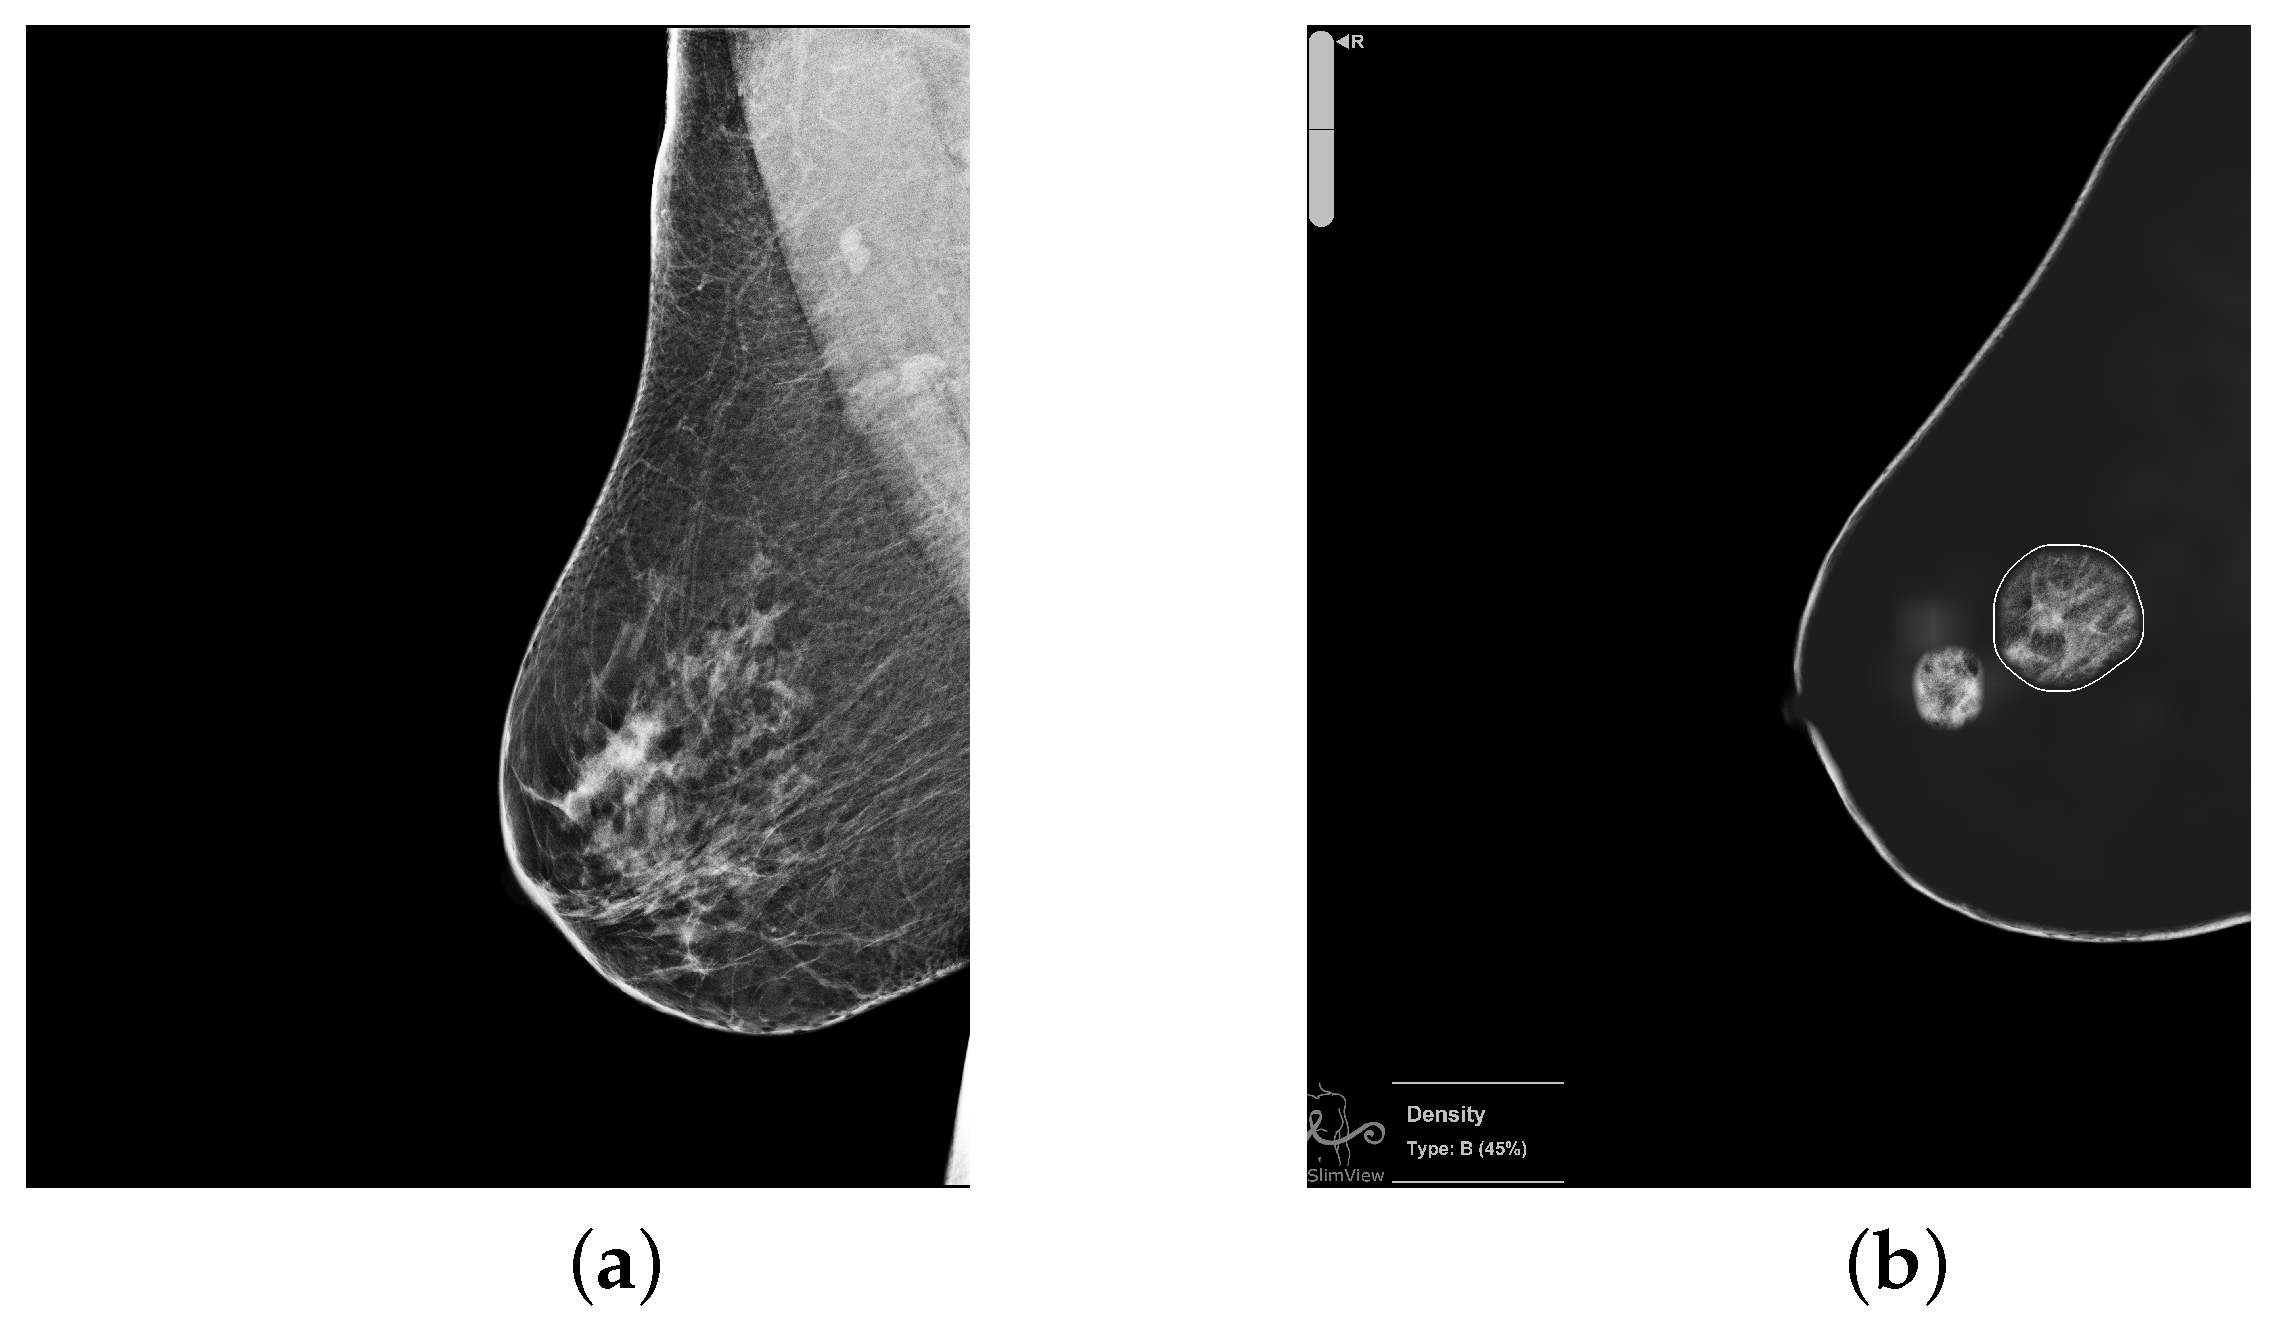

To illustrate the discrepancies between the AI algorithm and radiologists, Figure 3 presents a case classified by the algorithm as high-risk and by radiologists as low-risk. In the image on the left, the study was categorized by radiologists as BI-RADS 2, while the image on the right shows the finding detected by the software, which led to its classification as high-risk.

Figure 3. Example of disagreement between the algorithm and radiologists. The algorithm classified the case as high-risk, whereas the radiologists labeled it as low-risk (BI-RADS2). (a) Mammographic study categorized as BI-RADS 2 by radiologists. (b) Region detected by the algorithm that led to the high-risk classification.